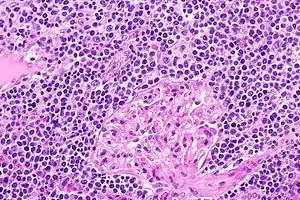

EMZL infiltrating kidney tissue.

The histopathologic (i.e. microscopic) examination of EMZL lesions typically reveals a vaguely nodular or diffuse pattern of cells. The malignant cells in these lesions have, in varying proportions, the morphology of small-to-medium-sized lymphocytes, centrocyte-like B cells, centroblast-like B cells, monocyte-like B cells, plasma cell-like B cells, and/or large B cells. When the large B cells form prominent sheets that are clearly separated from cells with the other, low-grade malignant morphologies, the disease may be transforming to the far more aggressive malignancy, diffuse large B-cell lymphoma. This transformation occurs in ~18% of patients at a median of 4–5 years after the original diagnosis of EMZL.[21] Immunophenotyping or the neoplastic large B cells in these lesions shows that they express CD20 but not CD3 surface membrane B cell marker proteins. The cells almost always express BCL2 and may express MNDA (~70% of cases), CD23 (~33% of cases) and CD5 (~20% of cases) marker proteins but do not express the cyclin D1 marker protein.,[21] the T-cell marker, CD10, or BCL6.[1]